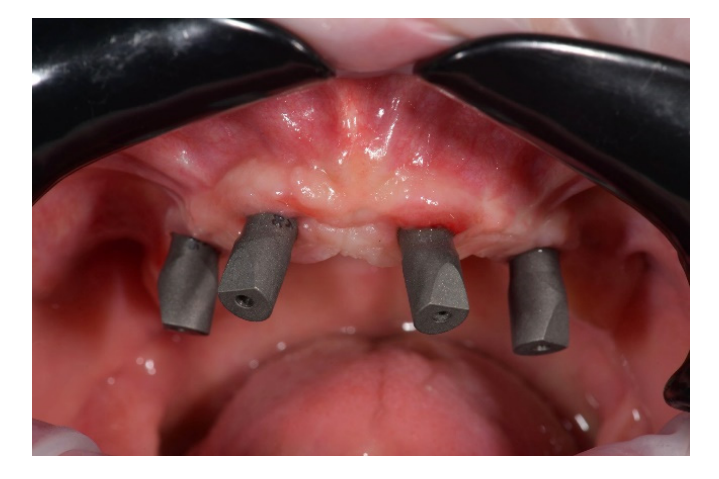

На этом этапе все последующие шаги, от планирования имплантации до доставки окончательных реставраций, были выполнены полностью в цифровом формате. После изготовления новых протезов пациенту был выполнен КТ-сканирование верхней и нижней челюстей по модифицированной технике двойного сканирования. Для последнего на нижнем протезе были применены трехмерные композитные маркеры, а для разделения зубных дуг использован восковый прикус. После этого было выполнено второе сканирование только нижнего протеза с использованием интраорального сканера (Medit i500). В нижней челюсти были запланированы два прямых импланта (Рисунок 4) и установлены (Рисунки 5 и 6) для удержания классического надпротеза.

В верхней челюсти было запланировано четыре имплантата по протоколу All-on-4 (Рисунок 7), чтобы поддерживать фиксированный, винтовой, зубной протез. Кроме того, также было запланировано уменьшение костной ткани верхней челюсти на три-четыре мм.

В день операции, после поднятия лоскута, была выполнена редукция кости с использованием базовой части хирургического шаблона в качестве ориентира (Рисунок 10). Затем были установлены два прямых передних имплантата и два наклонных задних имплантата в соответствии с протоколом All-on-4, используя имплантационную часть, без металлических втулок (Рисунок 11).